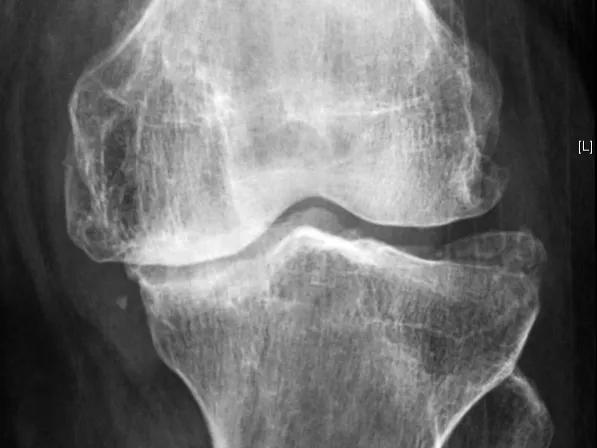

骨关节炎,也叫 退变性关节炎 或 老年性关节炎 ,其主要的病理基础就是 关节内软骨的磨损 ,随着年龄的增长、长期的使用以及外伤等因素,关节软骨表面不再光滑,磨损日渐加重,患者就会出现关节的疼痛、酸胀以及功能受限,严重的会导致残疾,它是老年人致残的主要原因之一。

但有一点要注意,那就是 骨关节炎患者的病情不能太重,适合早期和中期患者服用 ,如果经过检查患者的关节软骨磨损极其严重,关节间隙出现了明显的狭窄,关节周边已经有大量的骨赘形成,到了骨关节炎晚期的程度,就没有必要尝试了, 雄狮已经消失了,再补充养分也于事无补了 ,就是这个道理。

对于氨糖,我们就把它当做一个膳食补充剂来看待即可 ,没有必要强求它一定会达到什么样的效果, 不要对它产生过度的期望 。如果您的关节或半月板出现了问题,进行核磁检查明确诊断以后,是可以通过适当的服用氨基葡萄糖来观察能否帮助我们改善症状的,如果口服三个月左右的时间毫无效果就可以不要再服用了, 没必要强求,徒增风险和经济负担 。